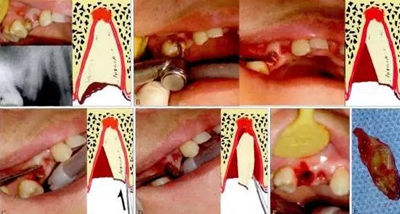

1.jpg

圖1 斜面原理。阻生的47已造成46遠(yuǎn)中牙根部分吸收(a),手術(shù)入路較為狹小而受限(b)。為了解除47脫位阻力,對牙體進(jìn)行分割(c)。將47牙切割成A和B,A部分因斜面(s)的存在可沿藍(lán)色箭頭方向順利脫位,并為B部分的松解創(chuàng)造空間,松解

后的B部分可通過多次分割取出(d)。如此可以盡量減少開窗去骨量,多保留鄰牙頸緣的骨質(zhì)(白色箭頭)。α:內(nèi)摩擦角;L:舌側(cè)。

2.jpg

圖2 榫楔原理。雙側(cè)阻生的上頜尖牙已導(dǎo)致雙側(cè)中切牙嚴(yán)重牙根吸收(a),為了避免在拔牙過程中對中切牙的擠壓,分割牙體時,按圖b中所示,將中間一段切割為上大下小的楔形(W),可以無阻力去除,然后再去除兩端的牙體(c),從而在最大

程度上保護(hù)了中切牙。在術(shù)后6月隨訪時,雙側(cè)中切牙已經(jīng)穩(wěn)固,其根尖部位骨質(zhì)恢復(fù)良好(d)。